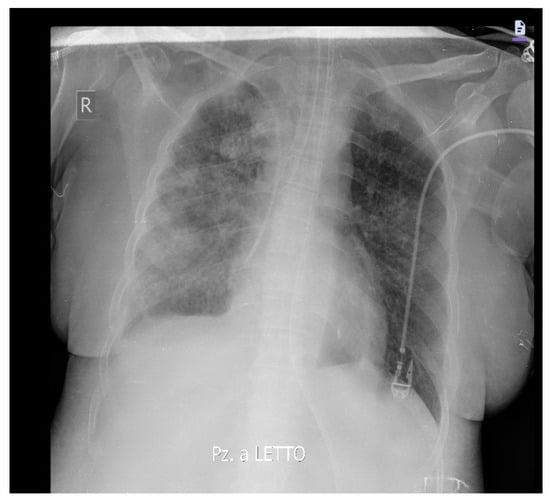

Likewise, an improvement in respiratory exchange and radiological images was observed (Figure 3).

Figure 3.

Chest X-ray 48 h after starting ganciclovir therapy shows an improvement in pulmonary densifications, more evident in the left lung.